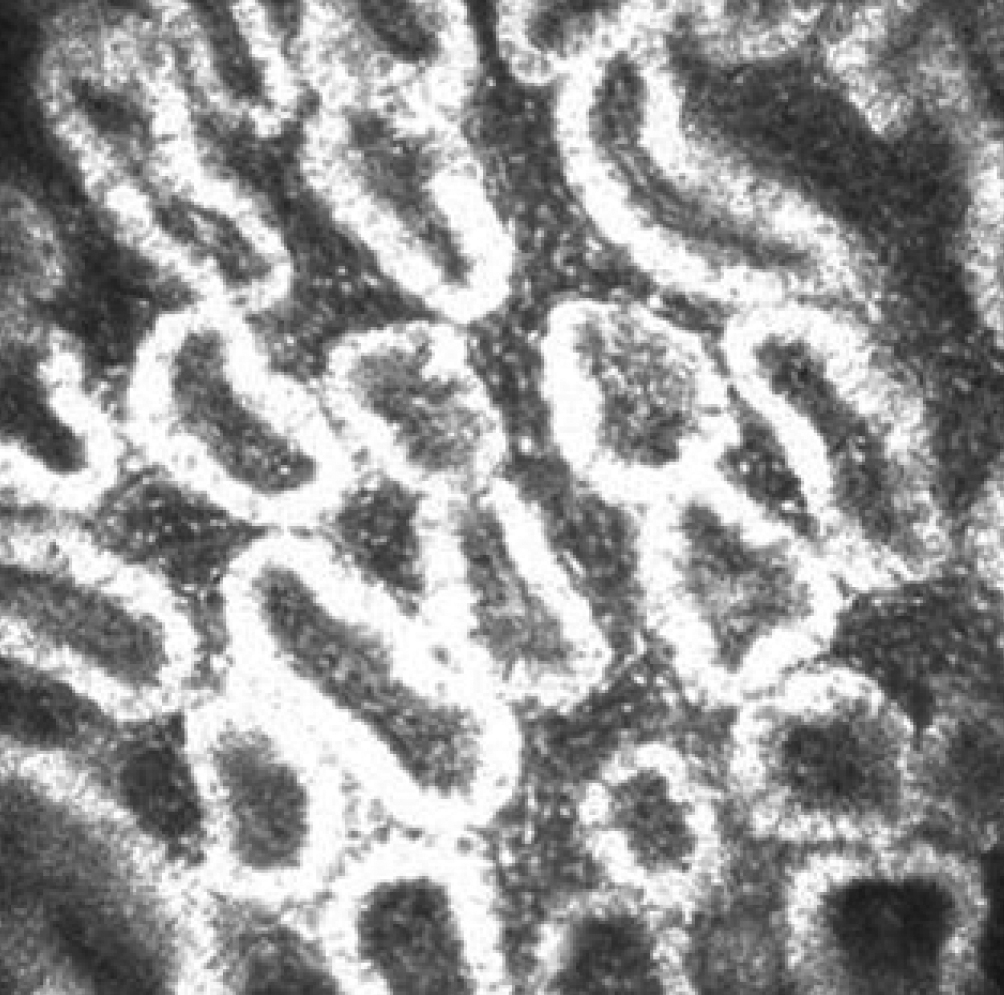

Figure 5 of Ban, Mol Vis 2011; 17:2533-2543.

Figure 5. Meibomian gland of non-DE/non-cGVHD recipient images observed by in vivo laser confocal microscopy. Non-DE/Non-cGVHD group, 61-year-old female (Case 6; Table 2). Note the presence of numerous and compact acinar units in patients without dry eye after HSCT.